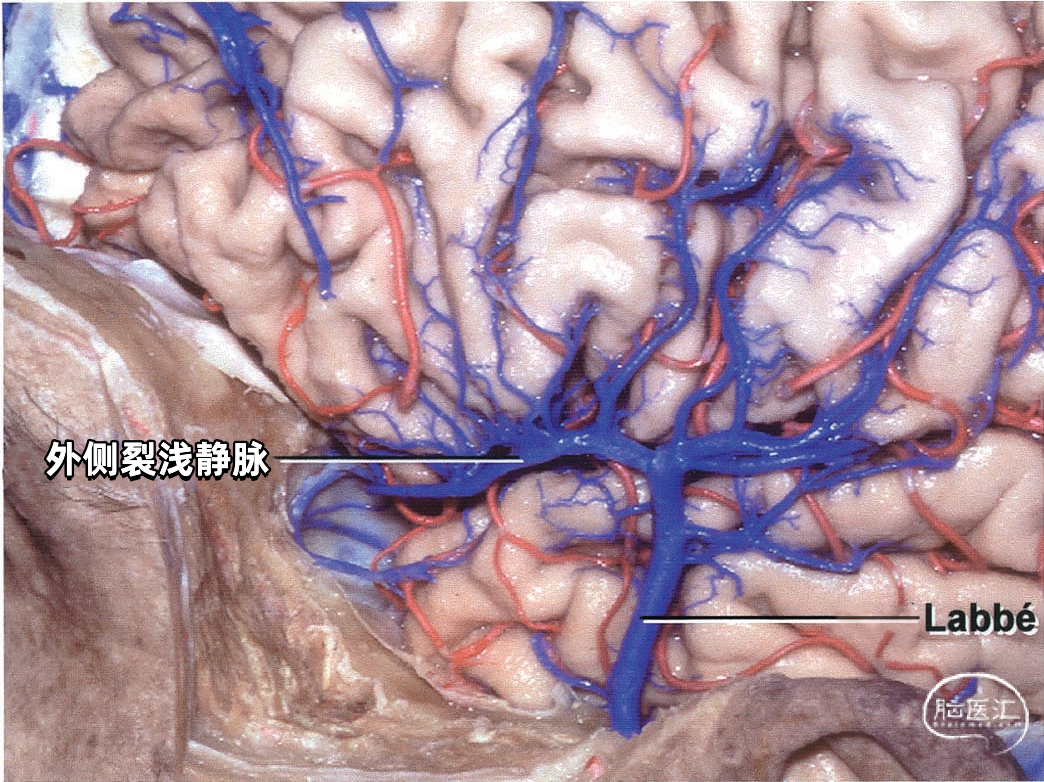

▼3.外侧裂浅静脉

外侧裂浅静脉通常起自外侧裂后端,沿外侧裂唇行向前下。它可能以两支起始,但通常在沿蝶骨嵴进入静脉窦之前融合为一支。 外侧裂浅静脉接受额外侧裂静脉、顶外侧裂静脉和颞外侧裂静脉的回流,并经常与Trolard静脉和Labbé静脉相吻合。它穿经覆盖外侧裂前端的蛛网膜,在蝶骨嵴内侧部下方加入蝶顶窦,或直接进入海绵窦。它也有可能离开外侧裂,围绕颞极,进入中颅窝底的硬膜窦,引流入岩上窦,或通过蝶骨的小孔出颅与翼静脉丛相交通。 如果外侧裂浅静脉细小或缺如,则相邻的静脉将代替引流其区域。起自外侧裂上唇的静脉,向上引流加入进入上矢状窦的静脉;起自外侧裂下唇的静脉,直接向后下,汇入颞叶下方的硬膜窦。如果外侧裂浅静脉的中部缺如,则静脉前部加入蝶骨嵴的硬膜窦,而后部则加入Trolard和Labbé吻合静脉。

下图示(左侧)粗大的外侧裂浅静脉,只与上矢状窦有较小的沟通支。但此区域的主要静脉引流通过颞叶中部的Labbé静脉

下图示外侧裂浅静脉向前汇入蝶骨嵴下方的蝶顶窦,向后汇入Labbé静脉。